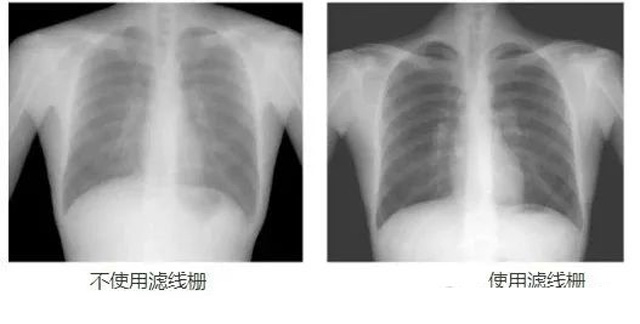

DR影像X射線在醫(yī)學檢查成像有著廣泛的使用。但是它的散射線影響成像質(zhì)量問題。濾線柵的發(fā)明使用很好的解決了這個問題,構造簡單鉛條粗,密度和柵比規(guī)格單一,能減散射線但吸收較多原發(fā)射線。伴隨這醫(yī)療影像設備技術的發(fā)展,這個濾線柵的工藝制造技術有改進,鉛條變薄,柵密度和柵比有更多的選擇。特別是材料方面有新組合,填充物也依不同成像要求優(yōu)化。特別是移動DR這類型的DR設備的出現(xiàn),濾線柵也設計成立方便拆卸形的,方便使用。被照體情況決定是否使用,更好平衡成像質(zhì)量與射線劑量。